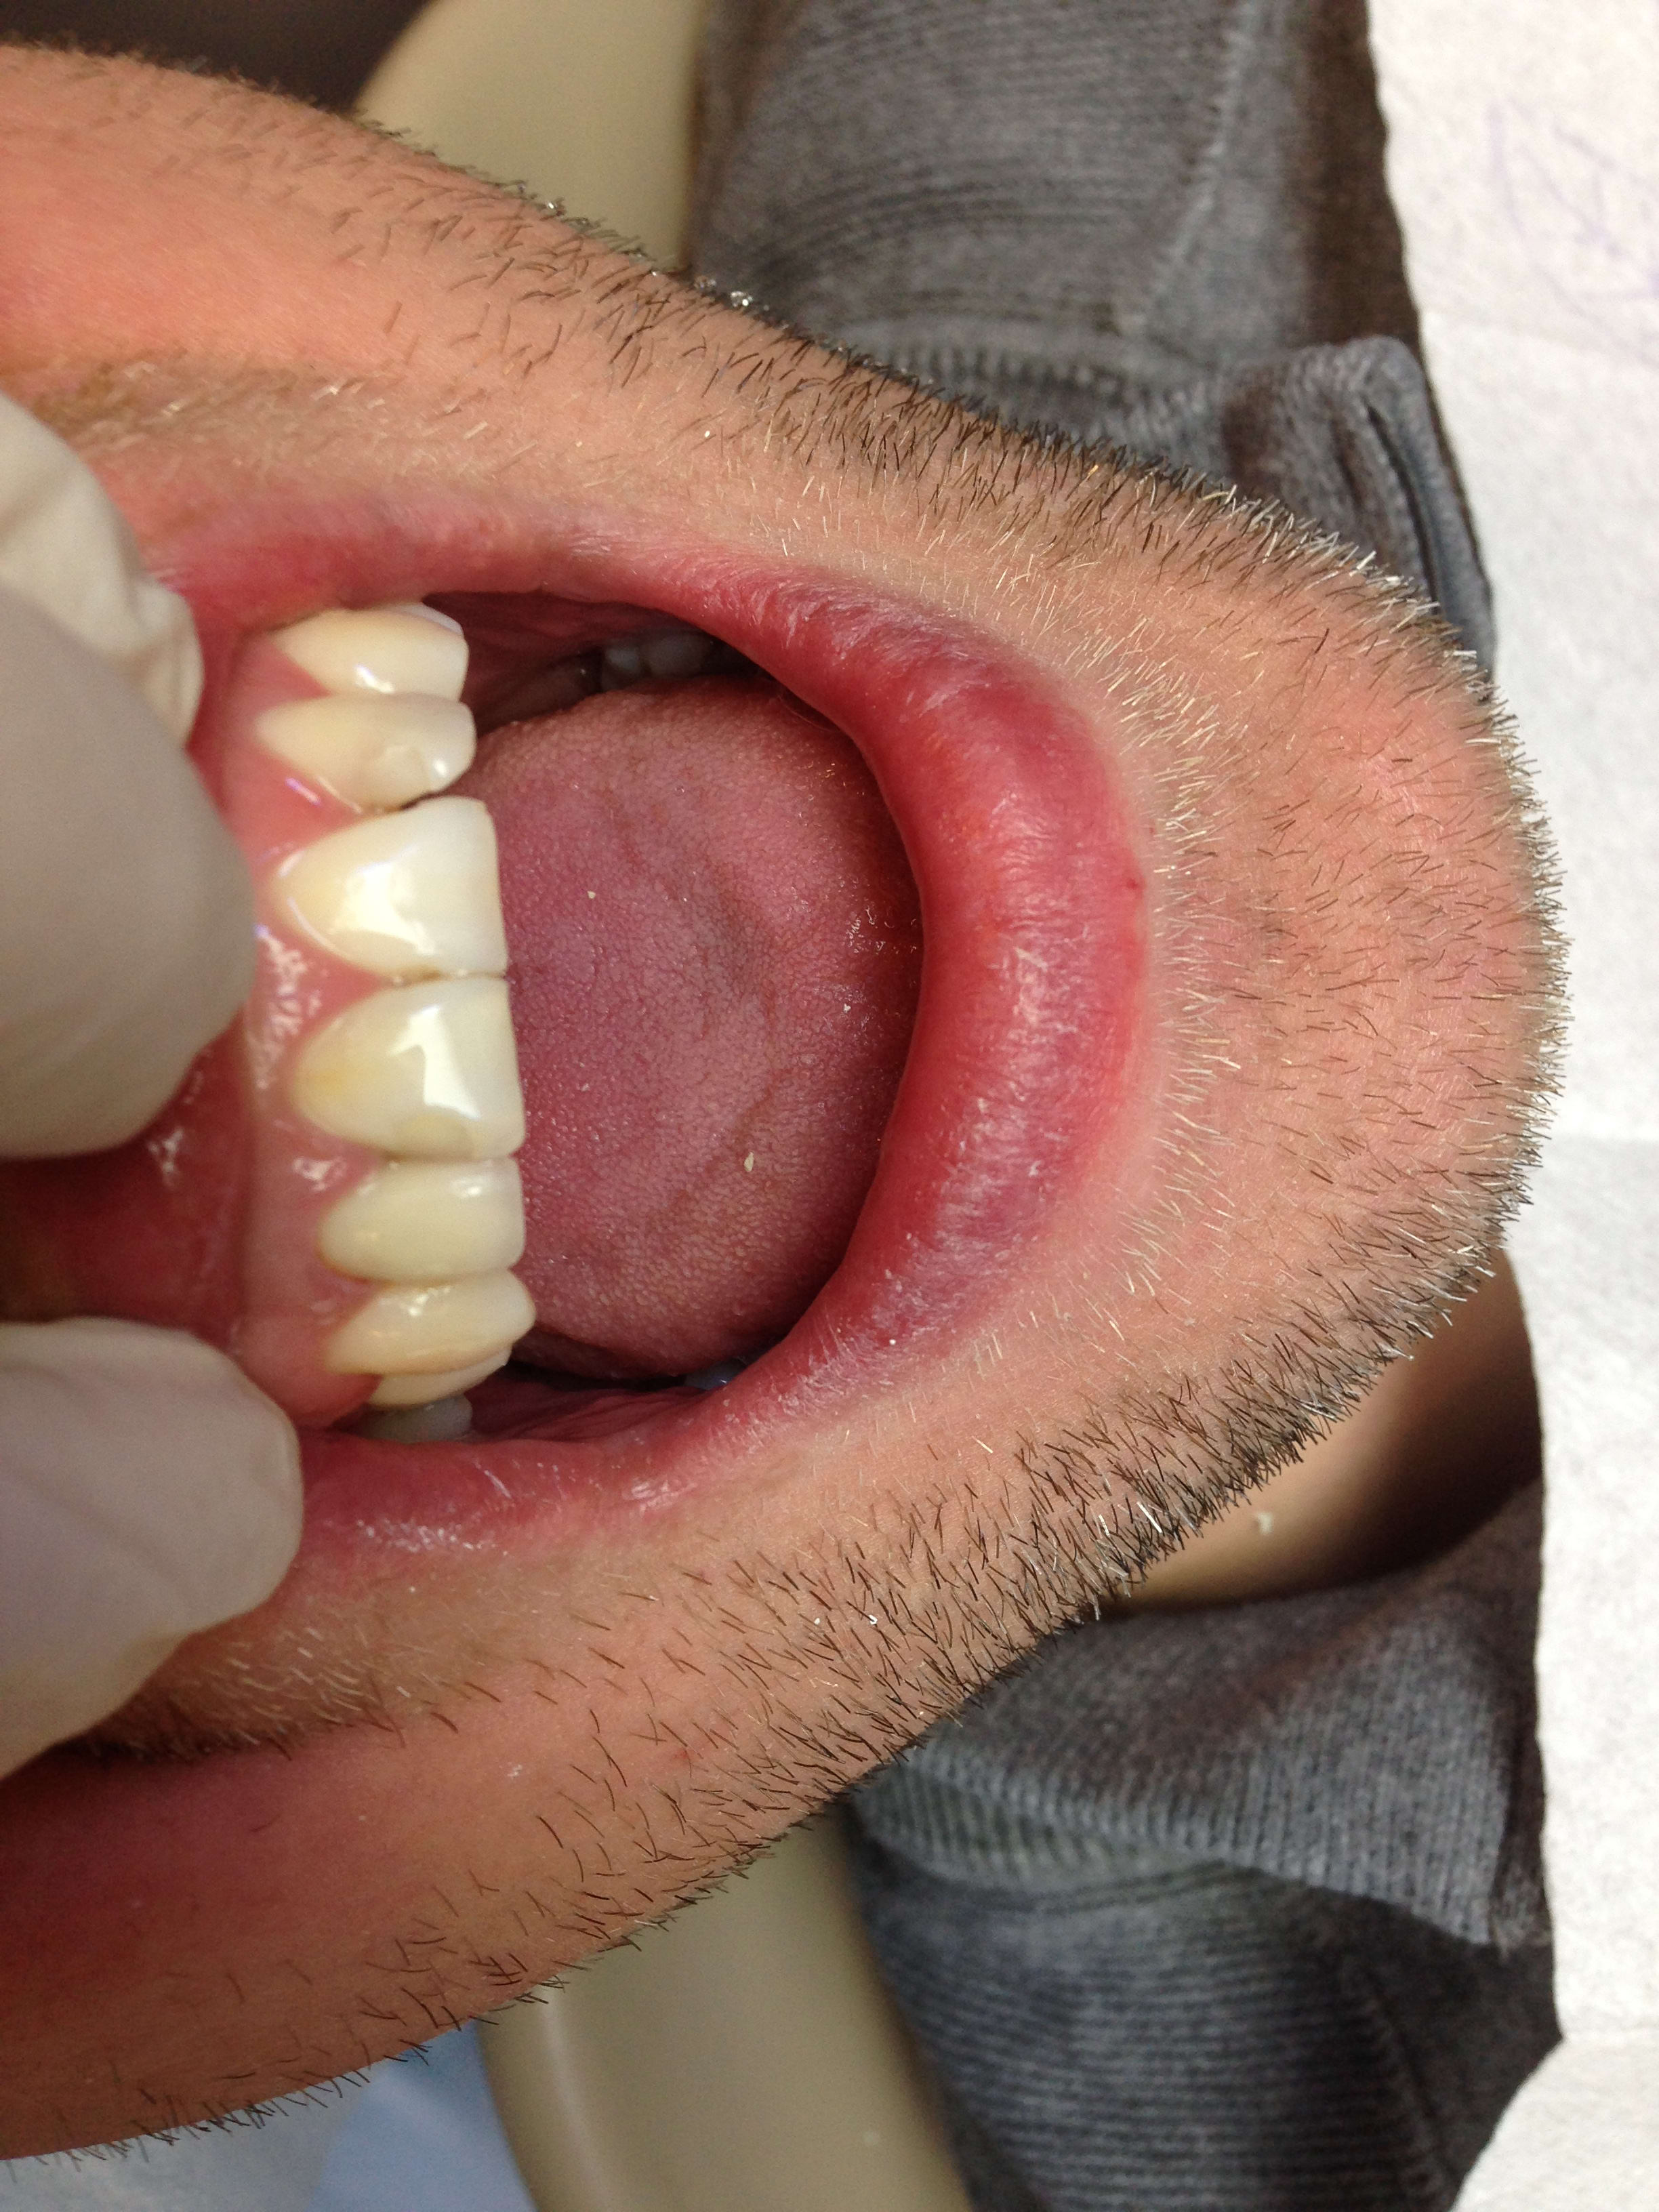

23/02/2017 à 14h25

Je suis en train de tester un autre labo spécialisé en "chinoiserie" comme le dit Enlaye.

Là je leur ai demandé de me faire une prémolaire ayant une forme de canine . (Absence de canine)